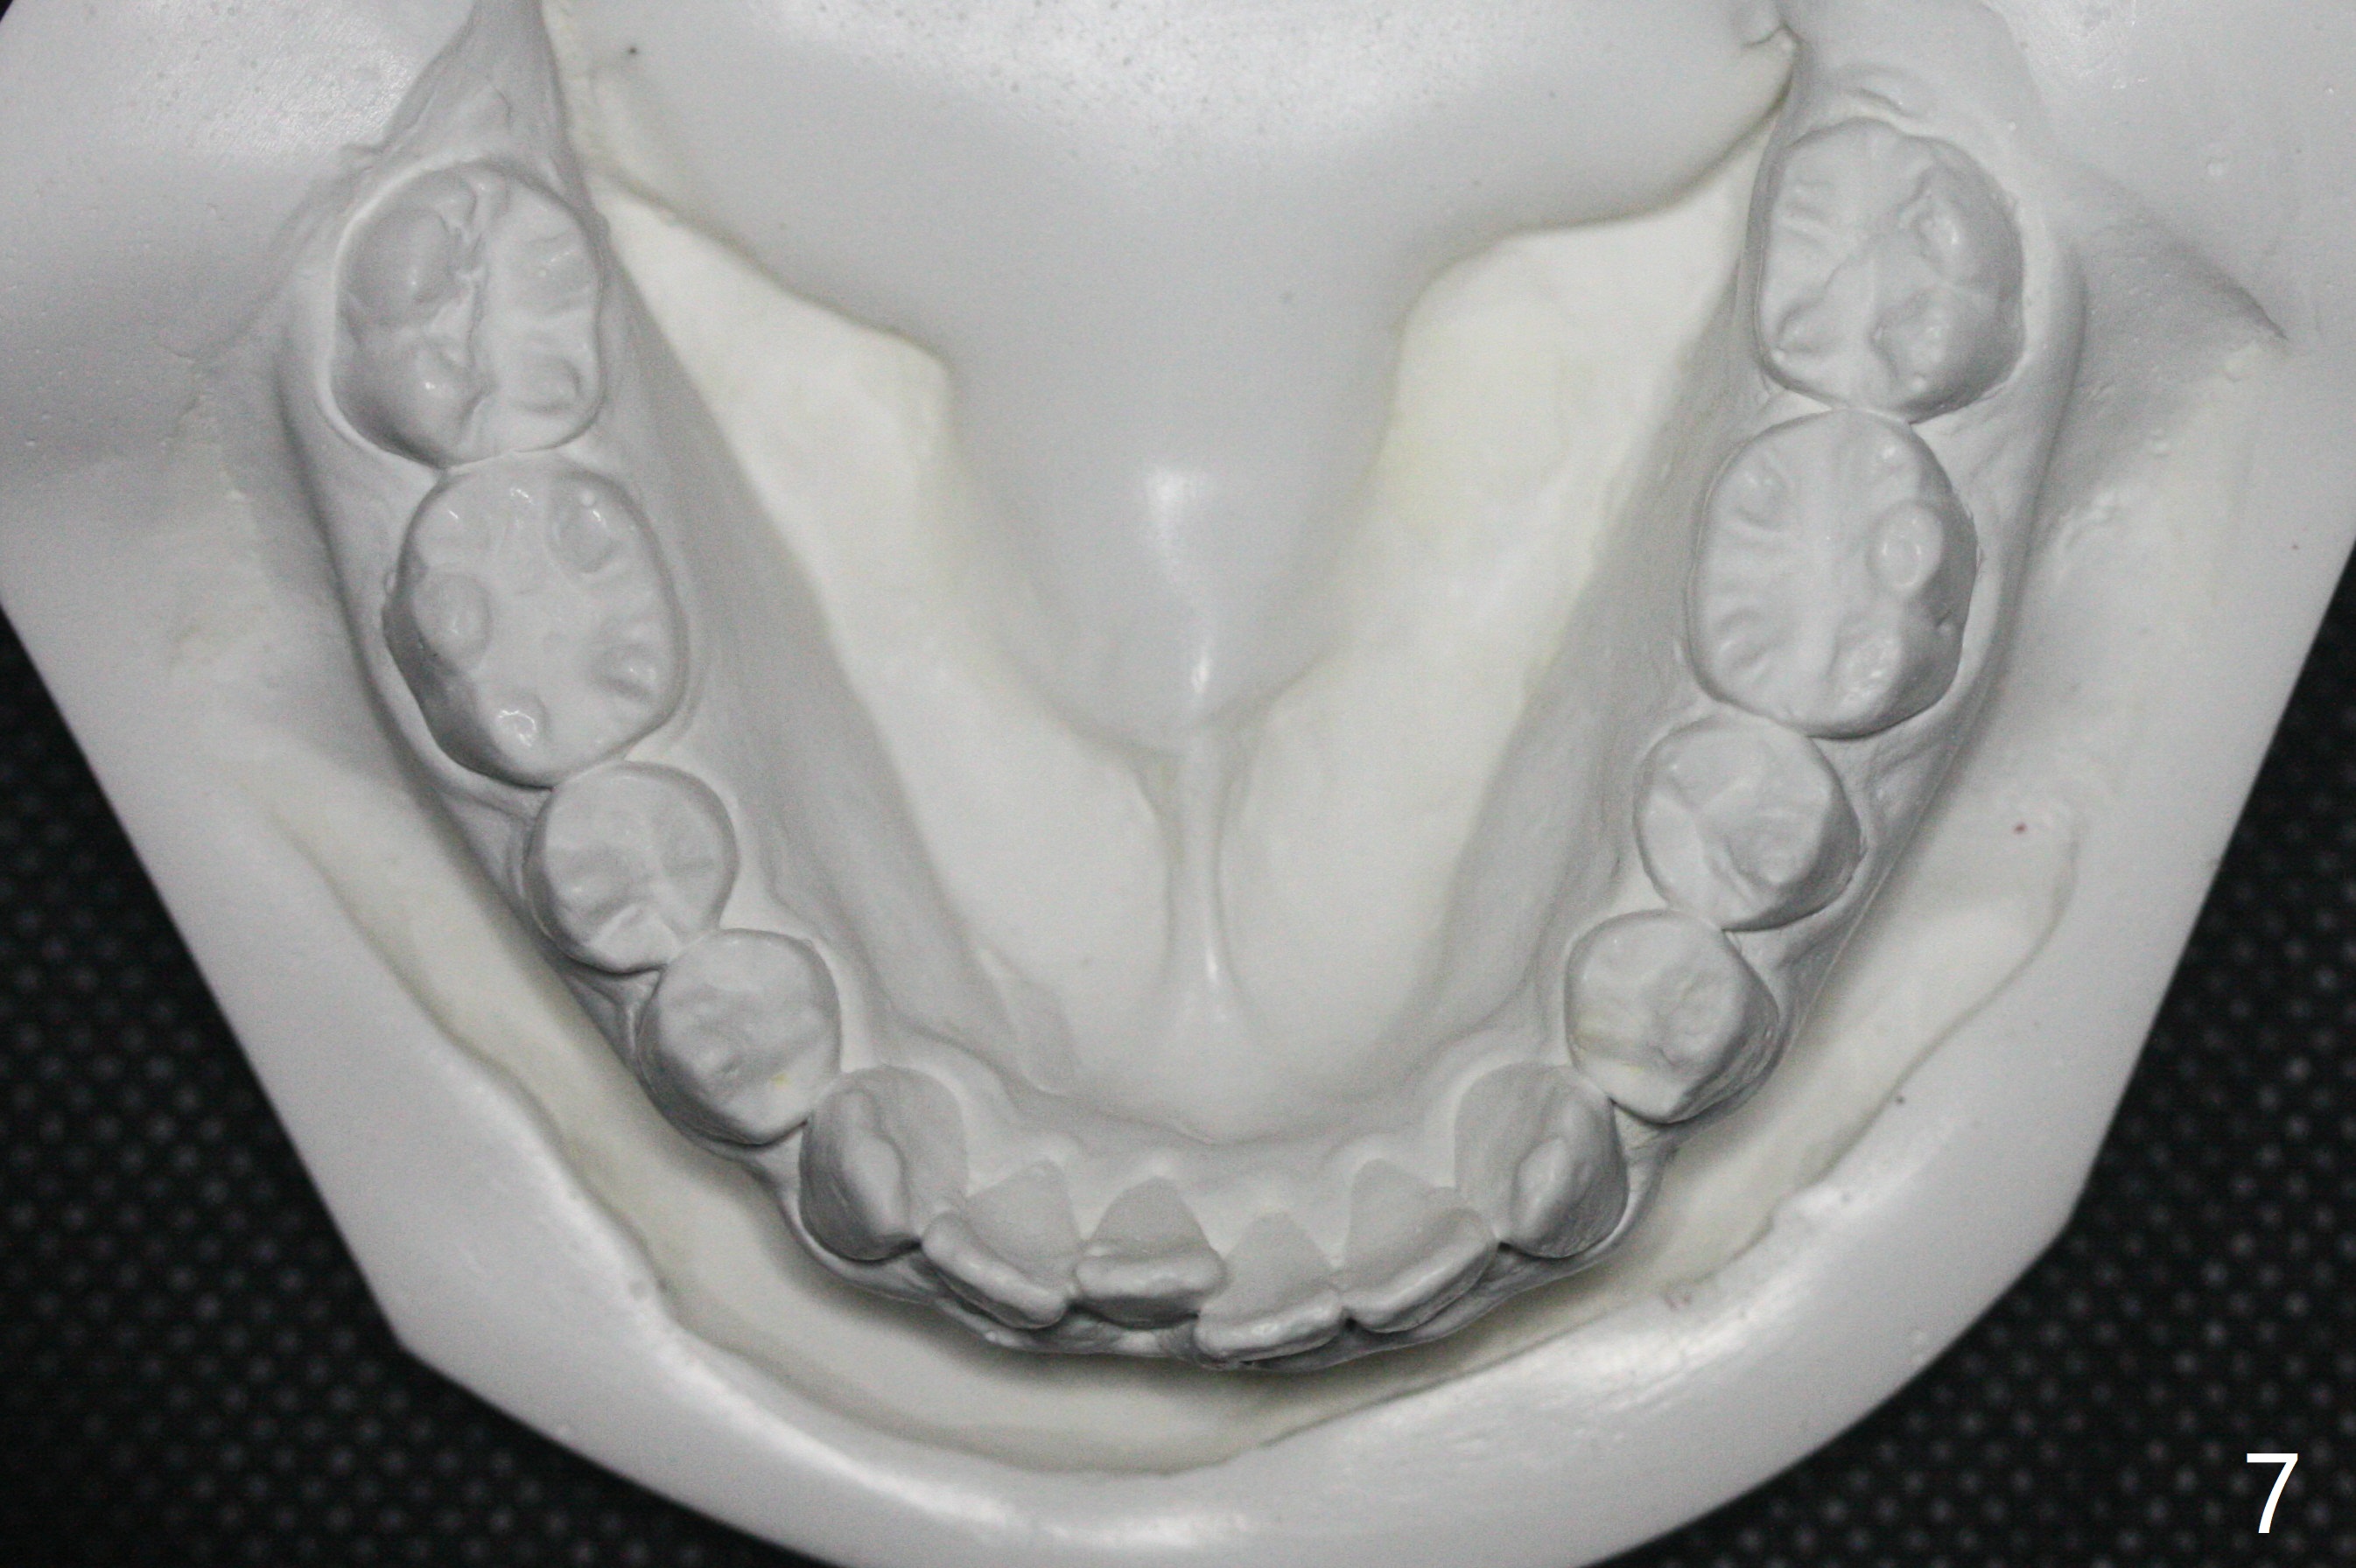

Bracketing for Congenital Missing Lateral